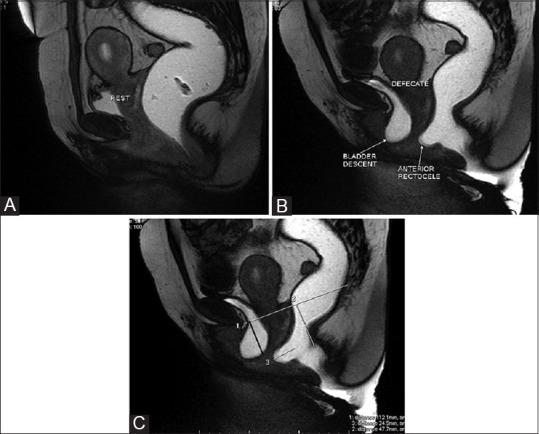

用于排便障碍综合征的磁共振排粪造影

MR defecography for obstructed defecation syndrome.

Patients with obstructed defecation syndrome (ODS) form an important subset of patients with chronic constipation. Evaluation and treatment of these patients has traditionally been difficult. Magnetic resonance defecography (MRD) is a very useful tool for the evaluation of these patients. We evaluated the scans and records of 192 consecutive patients who underwent MRD at our center between January 2011 and January 2012. Abnormal descent, rectoceles, rectorectal intussusceptions, enteroceles, and spastic perineum were observed in a large number of these patients, usually in various combinations. We discuss the technique, its advantages and limitations, and the normal findings and various pathologies.

摘要

排便梗阻综合征(ODS)患者是慢性便秘患者中的一个重要亚组。传统上,对这些患者的评估和治疗一直很困难。磁共振排粪造影(MRD)是评估这些患者的非常有用的工具。我们评估了2011年1月至2012年1月期间在我们中心接受MRD检查的192例连续患者的扫描结果和记录。在这些患者中,大量观察到异常下降、直肠膨出、直肠直肠套叠、肠膨出和会阴痉挛,通常是多种情况并存。我们讨论了该技术、其优点和局限性,以及正常表现和各种病变。